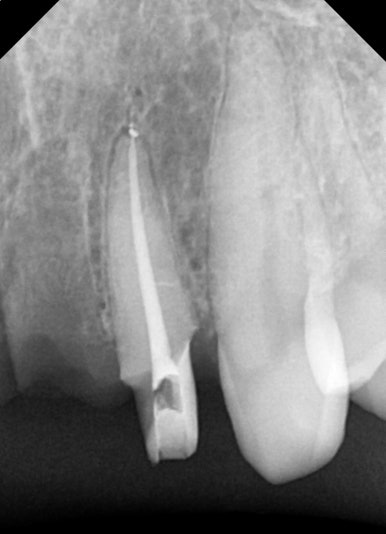

그중 뿌리만 남은 치아의 옆 치아(측절치, #22)도 금이 가있는 것을 발견을 했습니다.

아쉽게도 이 치아에도 금이 가있네요

(맨 우측 사진: 치료 중 X-ray 사진. 치아에 금이 간 것이 선명하게 보입니다.)